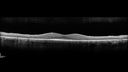

RP_anrus_071719_02.png

Retinitis Pigmentosa - Autosomal Recessive - 20/25 Vision344 views49 year old man 15 years ago he noticed decreased night vision.

VA OD: sc20/25 NscJ2

VA OS: sc20/25-2 NscJ2-1

IOP: TP: OD:17 OS:19

Genetic testing showed heterozygous for RPE65 - Probably not clinically important